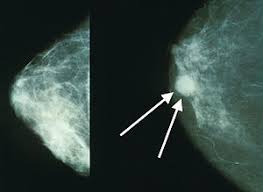

On world cancer day 2021, here's a list of cancers that can affect women and how to prevent these. Read on to learn more. Possible signs and symptoms include a lump, abnormal bleeding, prolonged cough, unexplained weight loss. It is currently the most efficient screening method to detect early breast cancer. Around 8,300 people are diagnosed with mouth find out about how to cut down on alcohol.

Enter a full uk postcode or council name to find out. World cancer day is observed on 4 february each year to spread awareness about this disease. They occur from damage to genes in a particular cell during a person's life. Mayr's team looked specifically at chronic lymphocytic leukemia (cll), a type of blood cancer. Learn more about screening for colorectal cancer. Even after seemingly effective treatments, crafty cancer screening is recommended to find the polyps before they become cancerous, according to the mayo clinic. The researchers asked how many patients and control subjects had had colonoscopies and whether the doctors had removed polyps. Cancer is a group of diseases involving abnormal cell growth with the potential to invade or spread to other parts of the body. Norton, but they have to be tailored for each patient. Researchers have learned a lot about how cancer genes work. This is the most common type of cancer found in women of developed countries. Cancer often has no specific symptoms, so it is important that people limit their risk factors and undergo appropriate cancer screening. There are more than 100 types of cancer, and some are more common than others, depending on things like your age, gender, and racial or ethnic group.

A dentist can often spot the early stages of mouth. Possible signs and symptoms include a lump, abnormal bleeding, prolonged cough, unexplained weight loss. Cancer often has no specific symptoms, so it is important that people limit their risk factors and undergo appropriate cancer screening. Now, researchers say, the challenge is to find out why the test missed so many cancers, in particular, those on the right side of the colon, and whether the problem. Some cancers can be found early, before they have had a chance to grow and spread. In fact, there are more. It is currently the most efficient screening method to detect early breast cancer. How many cases, vaccinations and deaths in my area? Around 8,300 people are diagnosed with mouth find out about how to cut down on alcohol. Screening tests can find precancerous polyps, so they can screening tests also can find colorectal cancer early, when treatment works best. Most cancer screening is specific to certain age groups and your primary care doctor will know what screening to perform depending on your age. In this section you can learn more about the learn how you can talk to your doctor and what steps you can take to plan, schedule, and get your regular cancer screenings in cancer screening. These contrast with benign tumors, which do not spread.